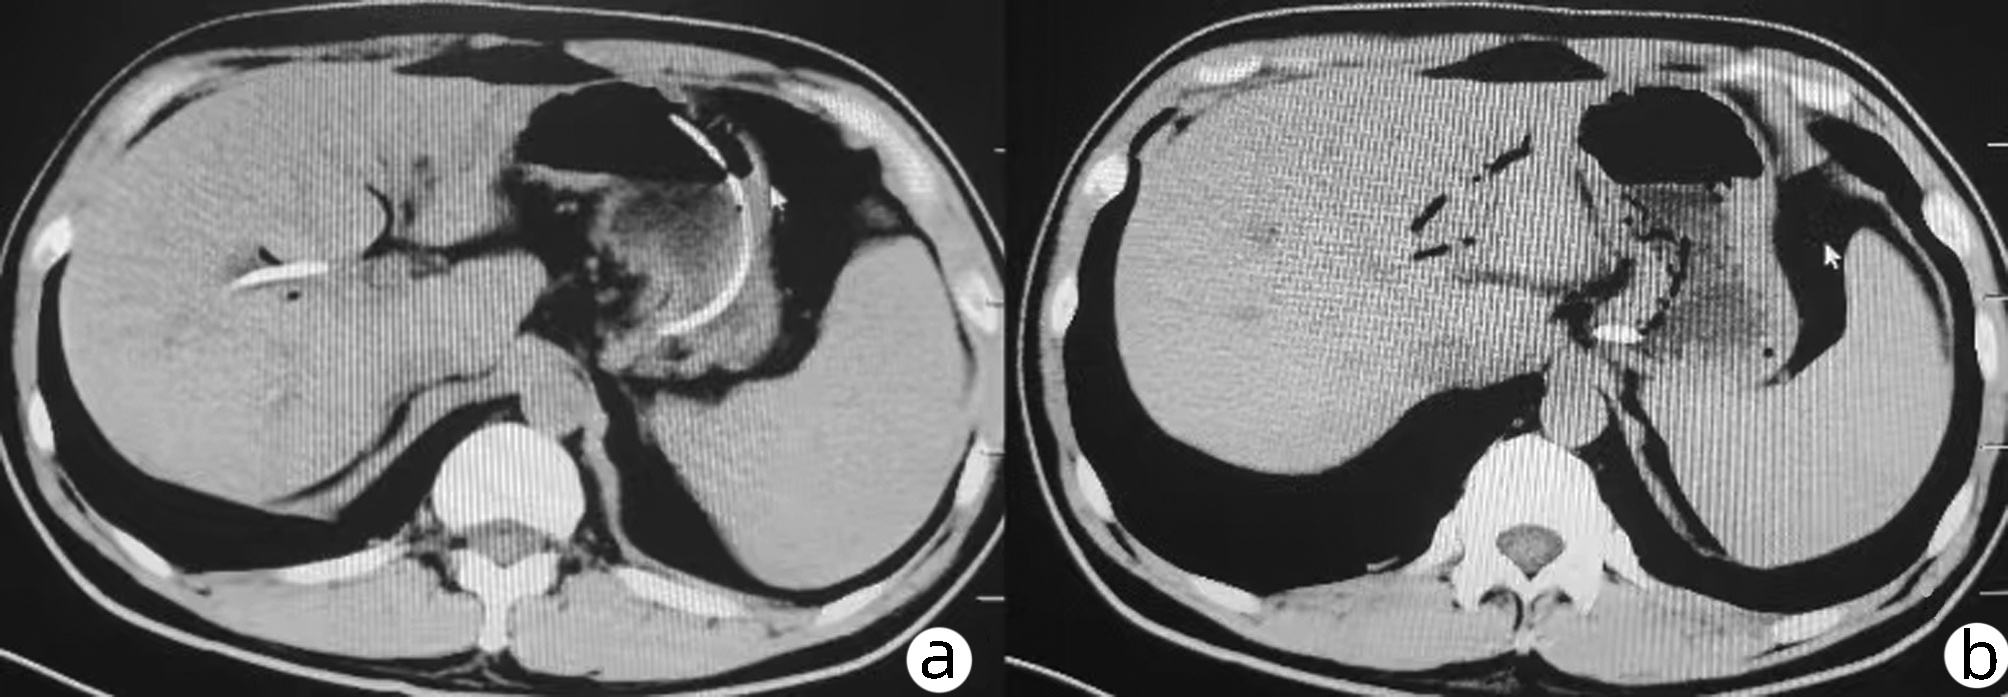

Journal of Viral Hepatitis|Reversibility of acute-on-chronic liver failure syndrome in hepatitis B virus-infected patients with and without prior decompensation

2022, 38(11): 2545-2545. DOI: 10.3969/j.issn.1001-5256.2022.11.gwjpwzjj1

Abstract(499) HTML (198) PDF (860KB)(72)

Abstract: